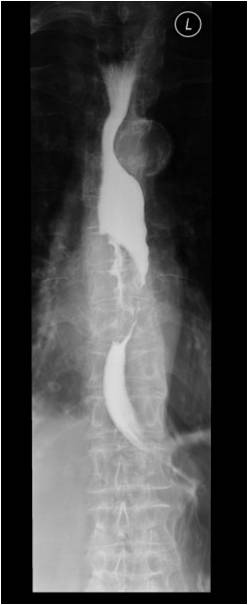

Рак пищевода

Fig.6.: Esophageal tumor.